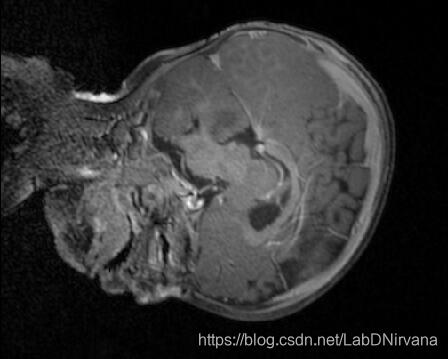

- 预测掩膜图

- 预测图:

这都是些啥子东西哦~~~~~~~~~~~